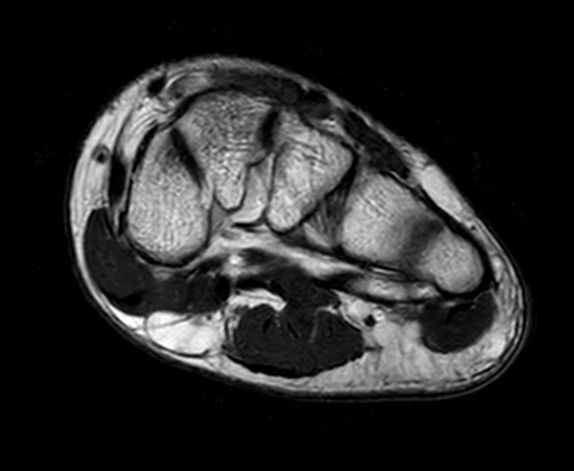

SmartSpeed Forefoot imaging

Suzukake Central Hospital, Japan

This forefoot ExamCard includes 3 orientations and several different contrasts. SmartSpeed is used to increase imaging speed while delivering outstanding image quality.

Axial T2w TSE

-

Axial T1w TSE

Axial STIR TSE